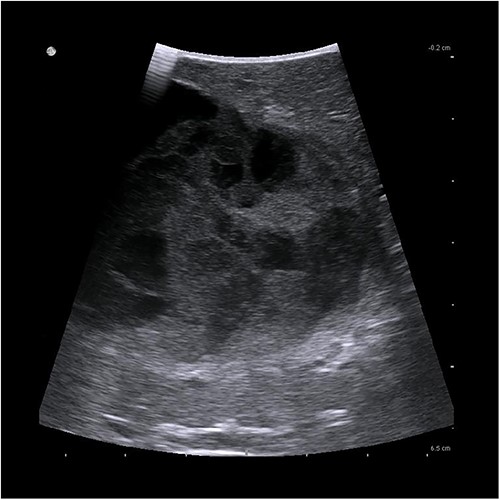

The presenting patient was a 40-year-old Brazilian native who had lived in Europe for ~26 years. Initially, the patient presented to her general practitioner with upper right quadrant pain. An ultrasound study (Fig. 1) showed a small hyperechoic lesion in segment VII measuring ~0.8 × 0.9 cm. Follow-up studies showed an expanding lesion with newer hyperechoic portions. In 2020 a liver specific magnetic resonance imaging (MRI) (Fig. 2) was performed. Here, again, the cyst was expanding, septated and had reached a size of 7.3 × 6 × 6.5 cm. A Echinococcus infection was considered, however, repetitive EIisa for Echinococcus sp./IgG was negative. The alpha protein was 2 ug/L, and well within normal limits. Due to increasing discomfort, an upper gastrointestinal tract endoscopy was performed. Here, gastritis and gastro-intestinal neoplasia could be excluded.

First documentation of liver cyst of the patient in ultrasound.